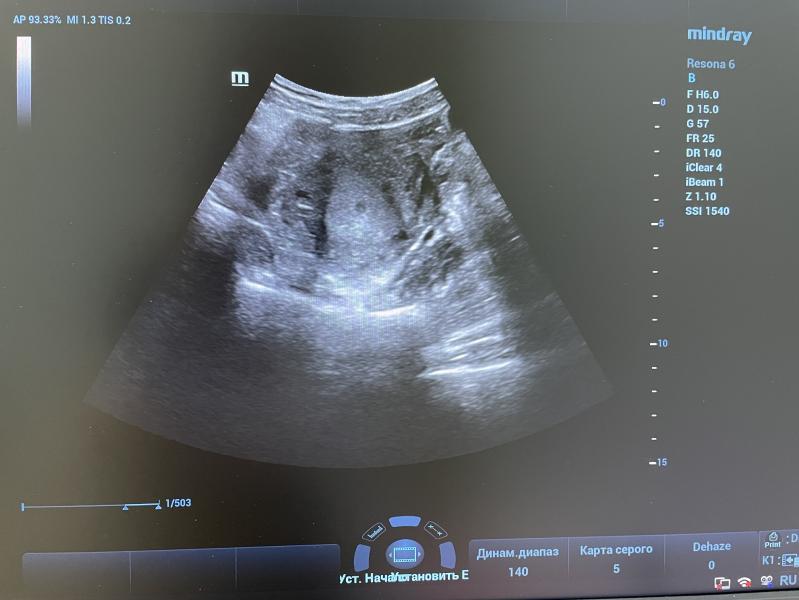

Плодное яйцо на 3-4 неделе беременности: размеры, развитие, что важно знать будущей маме?

Плодное яйцо.Беременность 3-4 Нед .